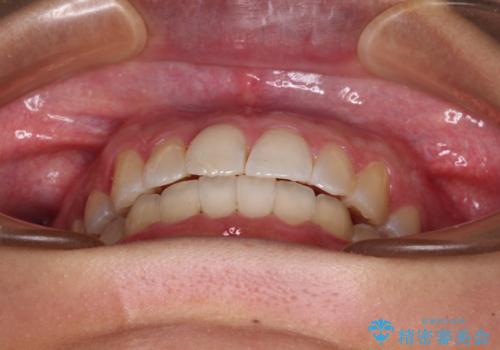

前歯のデコボコをインビザラインでスッキリと仕上げる

長時間のマウスピース装着に協力いただき、自然な口元に仕上げることができました。

気になっていた銀歯もオールセラミッククラウンで本物の歯のようになり、患者様には大変満足していただきました。